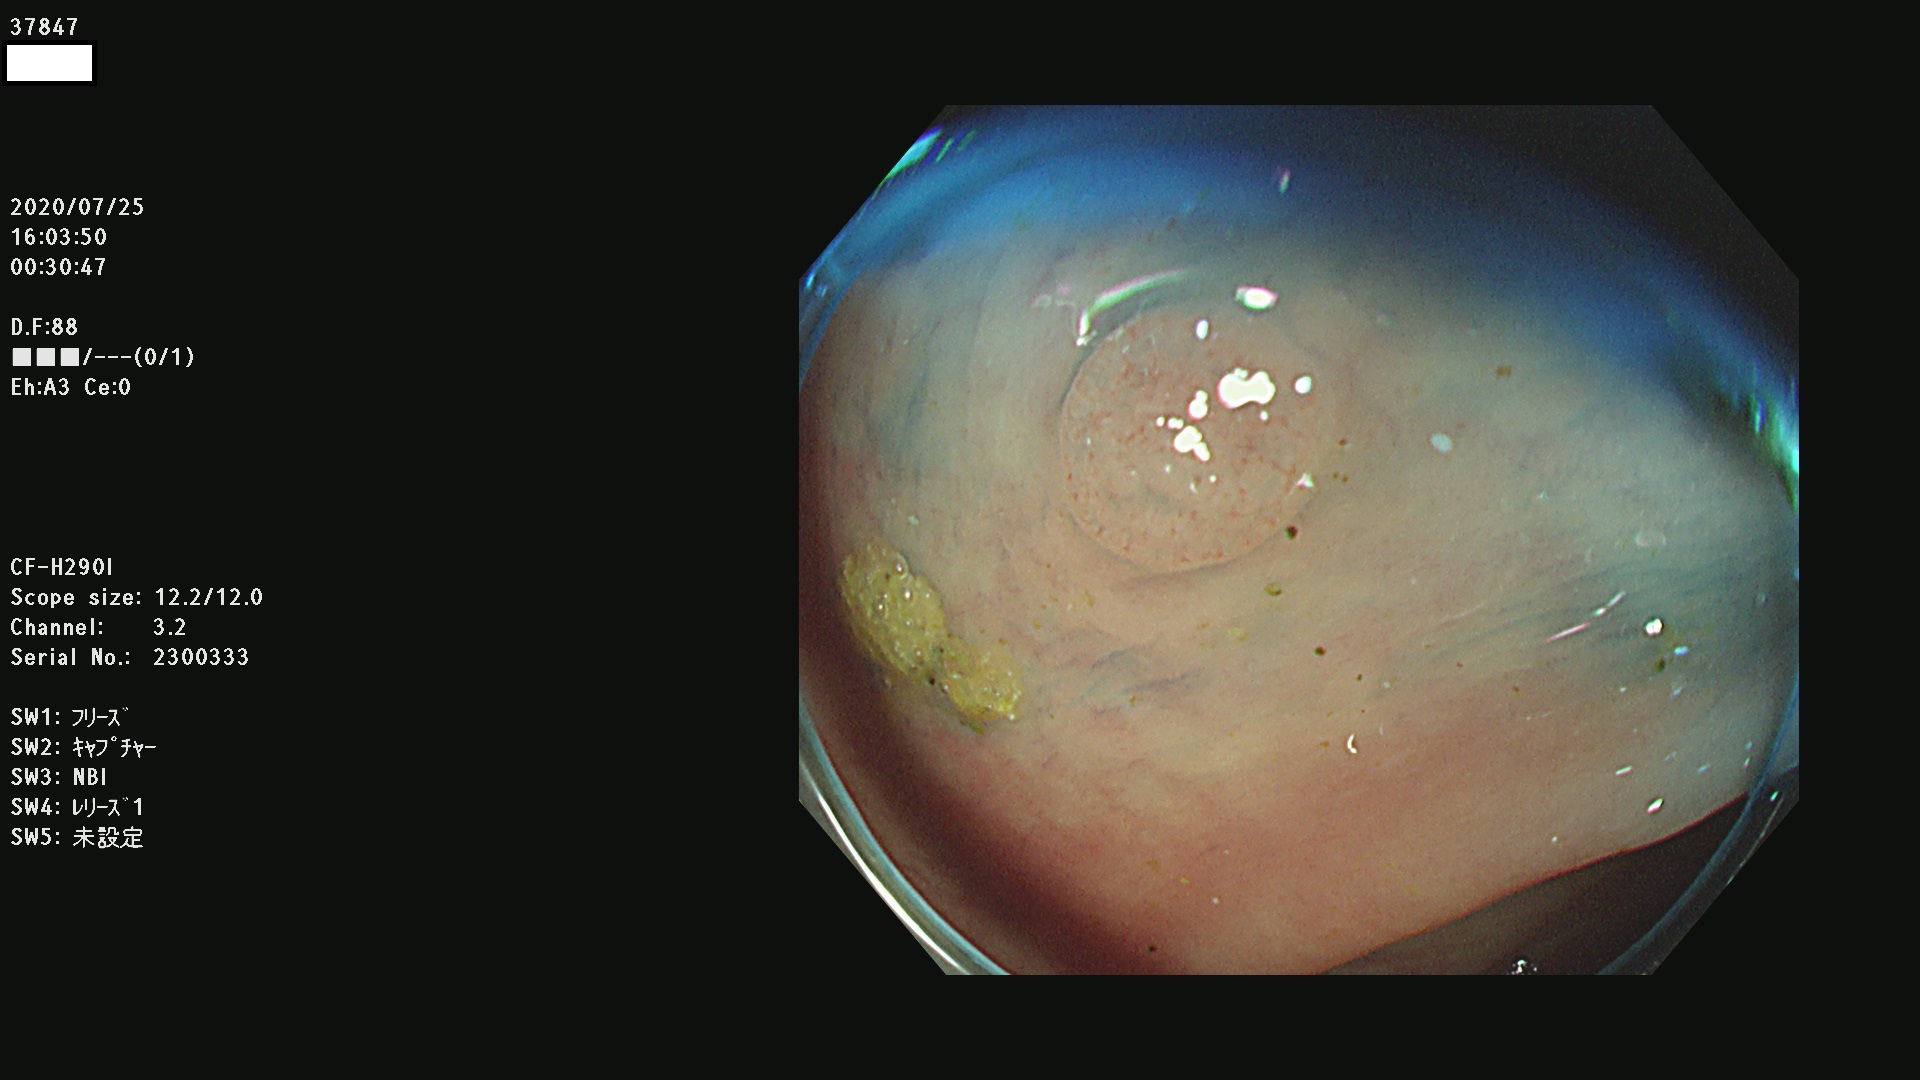

腺腫発見率 75 % (カルテ番号 37800〜37899の100名の方の検査結果で集計)大腸癌検診最新情報

以下のカルテ番号の方に腺腫(Adenoma,Group3〜5)が見つかりました(集計法)

37800(SSAPのみ) 37801 37802 37803 37804 37805 37806 37807 37808 37809(SSAPのみ) 37810 37811 37812 37813 37814 37815 37817 37818 37819 37820 37821 37822 37824 37825 37826 37827 37828 37829 37832 37833 37836 37837(SSAPのみ) 37839 37840 37842 37844 37845(SSAPのみ) 37847 37849 37850 37851 37852 37853(SSAPのみ) 37855 37856 37857 37860 37861 37862 37863 37864 37867 37868 37871 37874 37876 37877 37879 37880 37881 37882 37883 37886 37887 37888 37889 37890 37891 37892 37893 37894 37896 37897 37898 37899

発見困難で危険性の高い平坦型病変(上記100名より抽出) ![]()